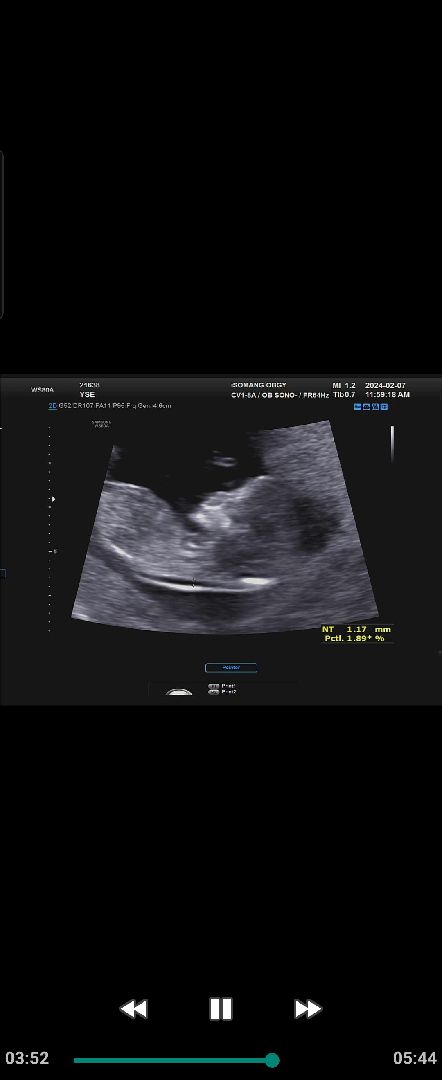

12주차 초음파

목투명대는 정상범위나왔는데 콧대는보이는데 코뼈가 안보인다는데 괜찮나요? 원장님은 아무 말씀 안하시지만 걱정되네요ㅜㅜ